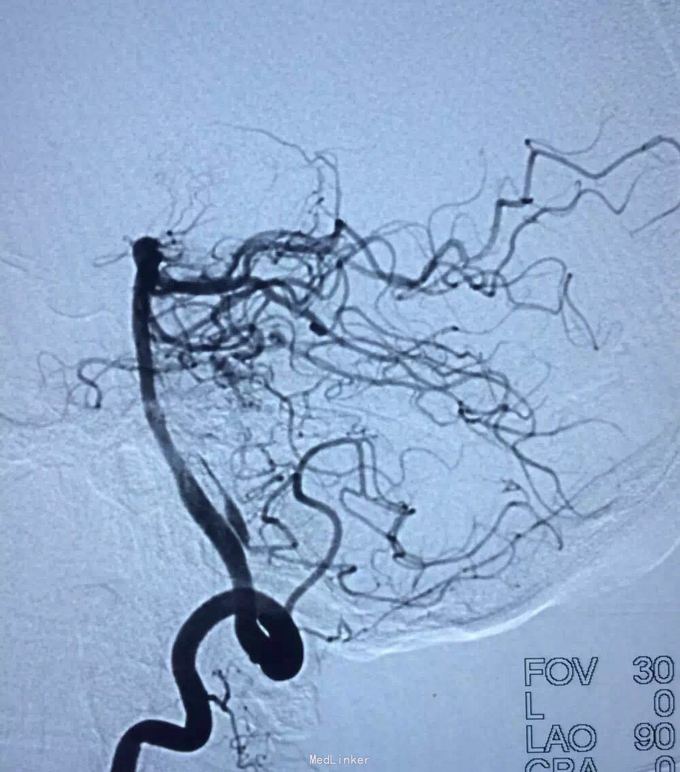

AVM

小脑出血

介入治疗